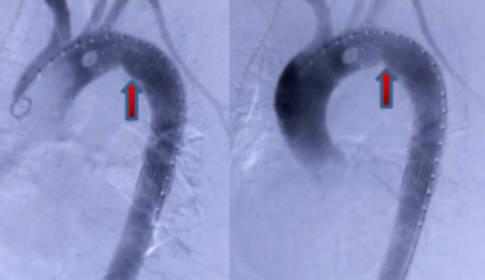

血管夾層是由于動脈中的血液,從血管內部破裂的地方進入了血管內外壁之間,而導致出現血管壁分離的現象,引起血管夾層的主要原因就是因為血管硬化,當血管硬化,結果導致血管的彈性非常差,如果同時伴隨著患者還有突發性的高血壓癥狀,那么突發性高血壓,再加上血管彈性差,就很容易出現血管夾層。

如果患者突然出現了突發性的高血壓,那么血管在高壓的血流沖擊過程中就會被撕開,這個時候血液就會在開口處涌入血管的內層和外層之間導致其分離,血管夾層最常見的是胸主動脈血管夾層,因為在血液被心臟泵出之后,就會向流向下肢,然后再下肢開始分布,這個時候血流的沖擊是非常大的,很容易造成胸主動脈血管的撕裂,從而形成胸主動脈血管夾層,一旦出現此種情況,患者往往會伴隨著突發性的胸背部疼痛而且疼痛非常的劇烈,這種疾病的死亡率非常高。